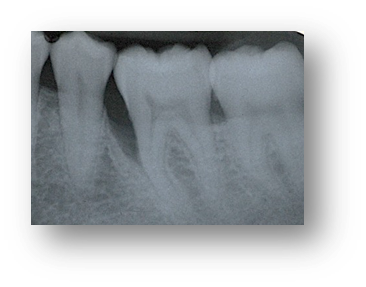

![]() | ![]() |

| Before and after surgery to reshape gums | X-ray showing results before and after bone graft surgery |